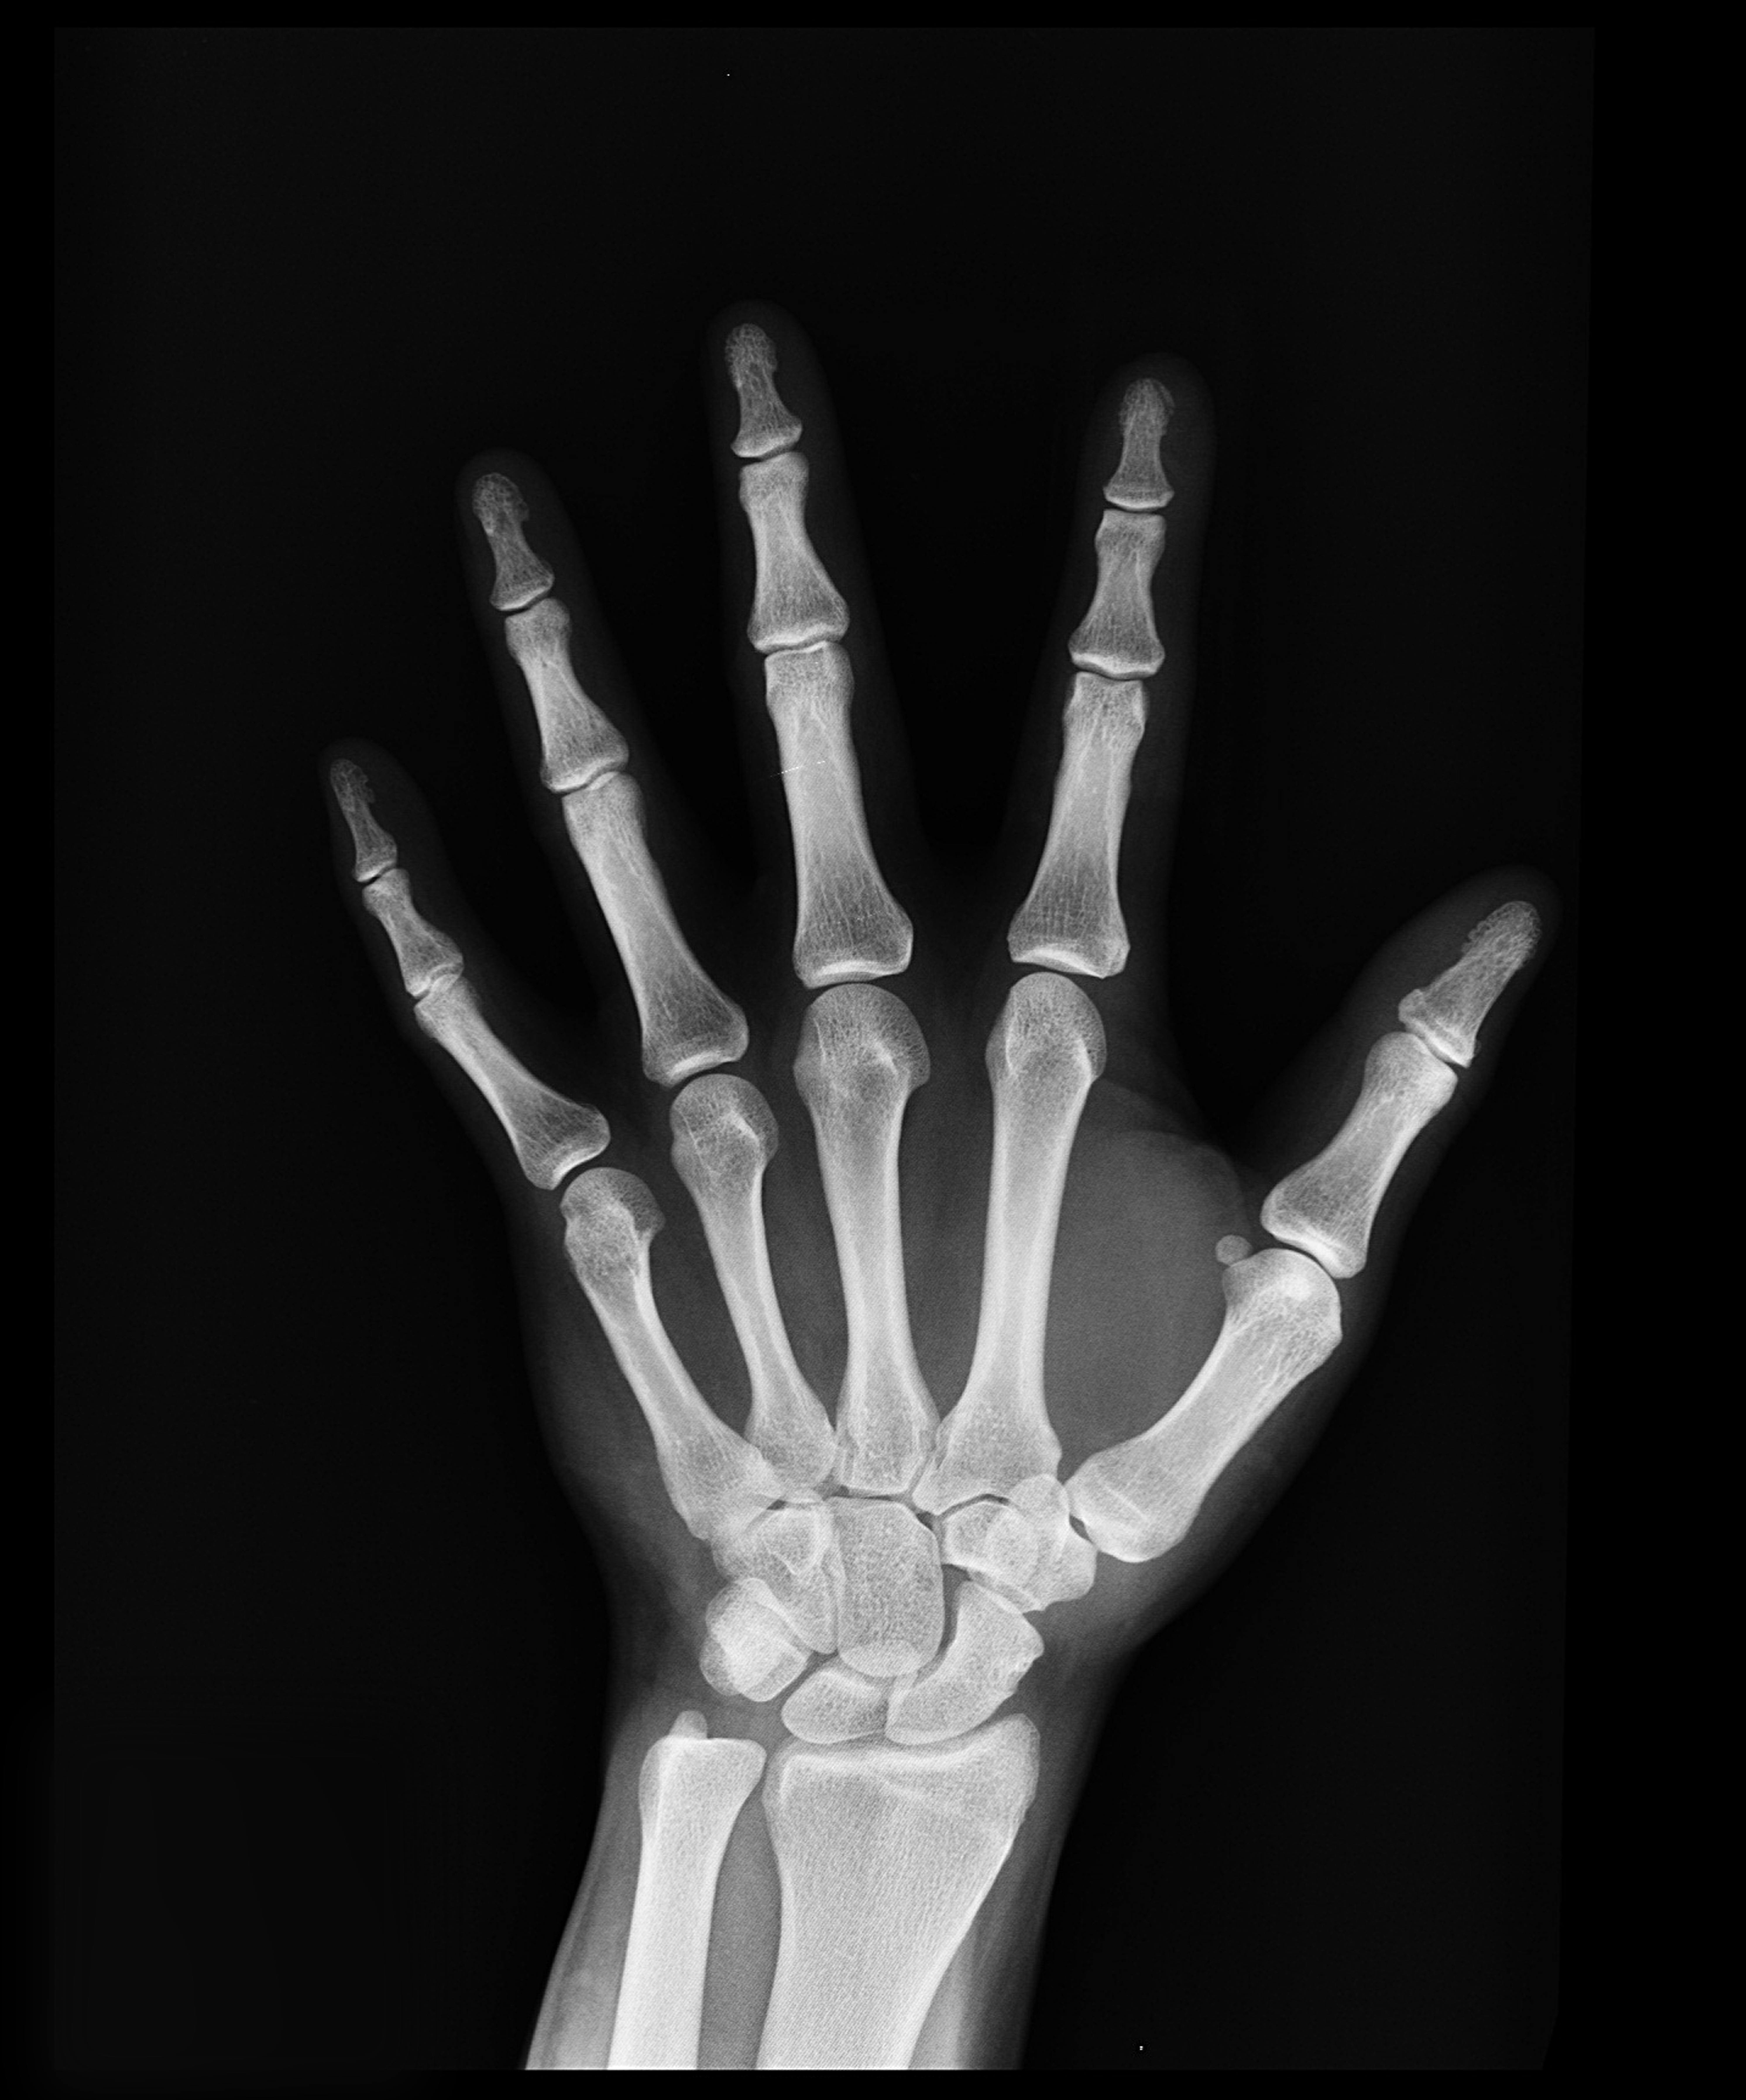

나이가 들면서 뼈 건강은 다양한 요인에 의해 영향을 받습니다. 청소년기에는 성장과 발달, 성인기에는 유지 관리, 중년 이후에는 골밀도 저하와 관련된 위험성이 커집니다. 또한, 한국인 연령대별 뼈 건강 상태와 지역 및 국가에 따른 관리법에도 차이가 존재합니다. 각 연령대별 뼈 건강의 위험 요인을 비교하고, 차이점을 분석하며, 효과적인 예방 및 관리법을 알아보겠습니다.

중년 이후부터는 골밀도가 자연스럽게 감소하기 시작하고, 골다공증 발병 위험이 증가합니다.

- 정기 검진: 골밀도 검사 및 정기 건강 검진 필수